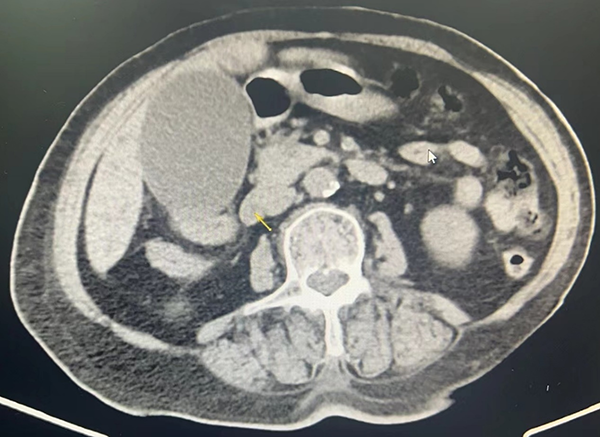

李奶奶入院消化內(nèi)科后,許統(tǒng)儉主任、朱祖安主任等共同評估病情并安排ERCP術(shù)。朱祖安主任在施行ERCP術(shù)中發(fā)現(xiàn),患者情況遠(yuǎn)比想象中復(fù)雜得多,除了要時(shí)刻關(guān)注患者術(shù)中的反應(yīng)與生命體征外,因其十二指腸乳頭較小沒有支撐點(diǎn),給經(jīng)乳頭插管增加了難度。膽管插管成功后,X-Ray造影顯示膽總管擴(kuò)張,直徑約22mm,內(nèi)可見多發(fā)結(jié)石影,最大約15mm,行乳頭切開,置入7cm*8Fr雙豬尾膽管塑料支架引流膽汁,很快緩解了膽管梗阻,避免了病情加重的風(fēng)險(xiǎn)。術(shù)后患者和家屬連連感謝,為徐醫(yī)附院消化內(nèi)科點(diǎn)贊!